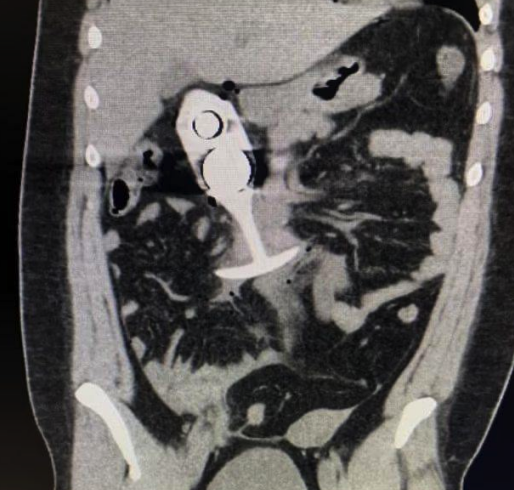

Инцидент, который сложно забыть: девушка отправилась на МРТ с игрушкой внутри, и всё закончилось трагикомическим кошмаром. Что произошло? • Опасная забывчивость: • Британка отправилась на томографию, забыв вынуть интимный аксессуар. • Металл в игрушке: • Внутри силиконовой пробки оказалось металлическое ядро. Сильный магнит томографа моментально притянул его, пробив брюшную полость девушки. • Моментальная угроза: • Металл стал причиной серьёзной внутренней травмы — пациентка чудом осталась жива. Почему это важно? 1. Неочевидная опасность: • Даже на вид безопасные вещи могут содержать металл, который становится смертельно опасным при взаимодействии с МРТ. 2. Внимание к деталям: • Перед любой процедурой с использованием магнитного поля важно уведомлять врачей о любых металлических предметах в теле. 3. Проблема современных игрушек: • Многие из них содержат металлические компоненты, о которых пользователи могут не знать. Итог «Богатый внутренний мир» в прямом смысле едва не стоил девушке

• Внутри силиконовой пробки оказалось металлическое ядро. Сильный магнит томографа моментально притянул его, пробив брюшную полость девушки.

• Металл стал причиной серьёзной внутренней травмы — пациентка чудом осталась жива.